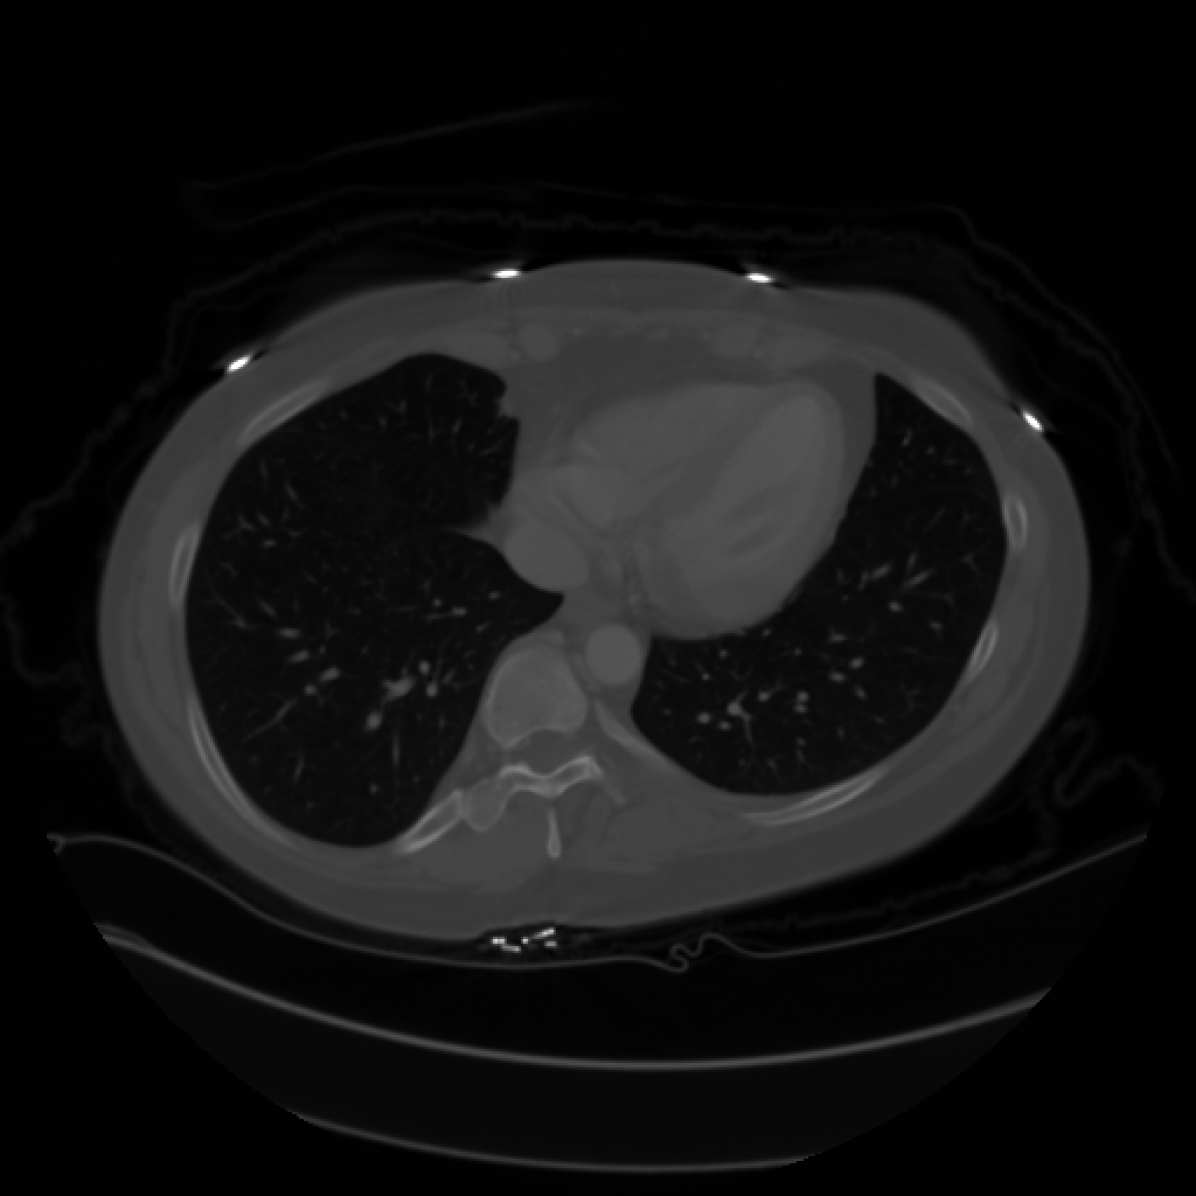

In this section we will show qualitative results of DINOv2 features using principal component analysis (PCA) performed on DINOv2 patch features on X-ray, CT, and MRI scans, following the method delineated in [8]. We will also provide organ segmentation results of linear compared U-Net decoders.

PCA visualization. Figure 2 shows the first three PCA components. The PCA is computed between patches of images that are in the same column, and the first 3 components are shown for X-ray, CT, and MRI scans. Thresholding is used on the first PCA component to remove the background. Just like in natural images [8], the colors of the three PCA components correspond well with the same parts of images in the same category. This is an easier task however, compared to natural images, because there is less variability between examinations on medical images compared to natural images.